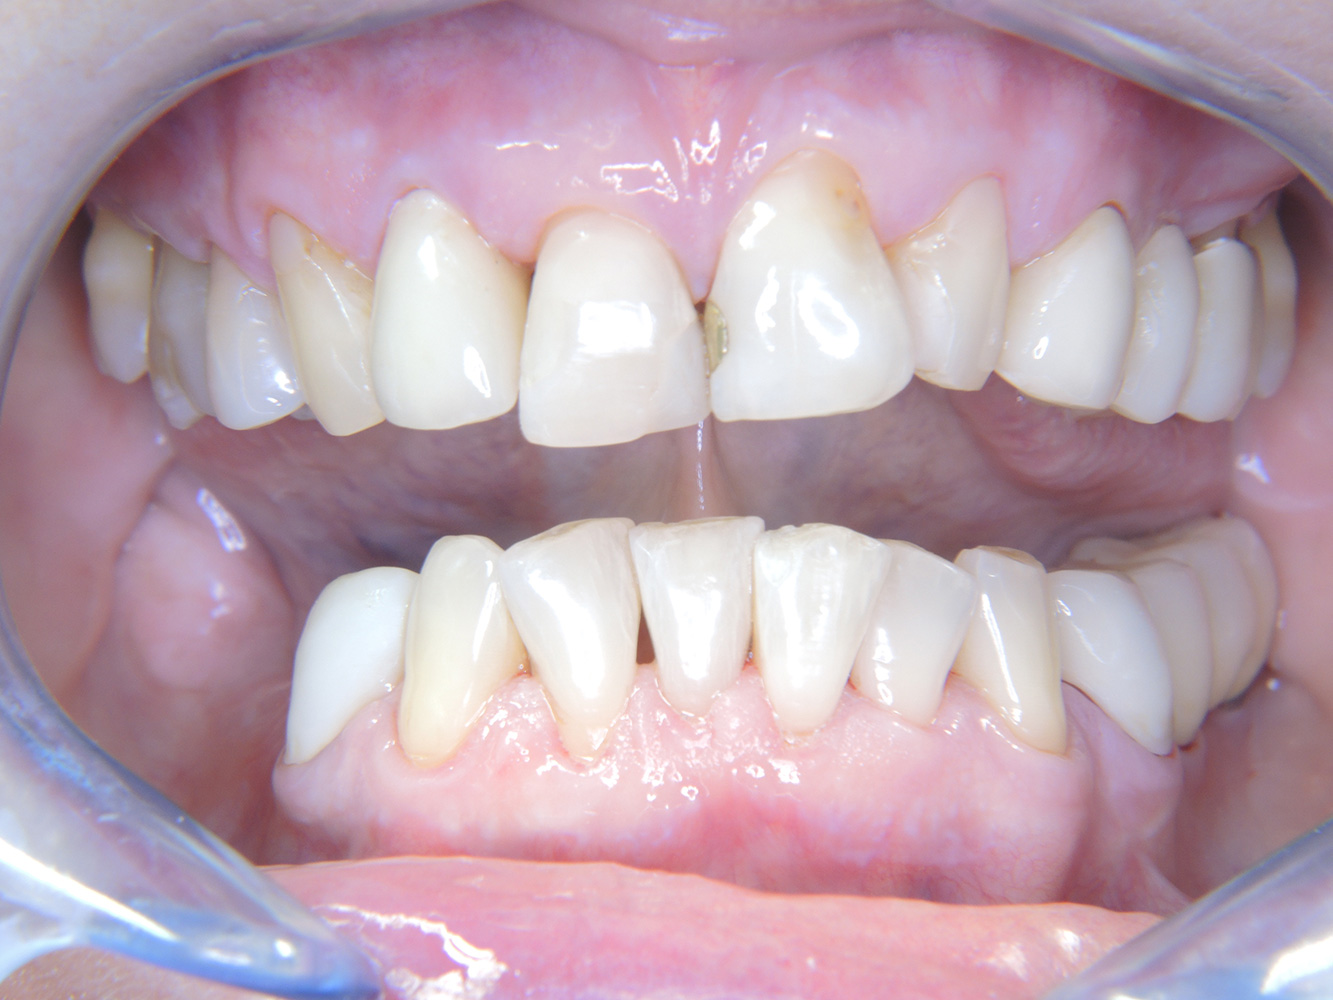

La paciente de 68 años no tiene enfermedades previas relevantes de la salud general ni toma medicación; sus hábitos alimentarios tampoco suponen un riesgo especial. La paciente tiene dos implantes (tercer cuadrante, desde hace cinco años) y una enfermedad previa periodontal (periodontitis en etapa IV, grado B) con pérdida dental. Actualmente las condiciones periodontales son estables, pero la periodontitis aumenta de manera determinante las complicaciones biológicas cuando se realizan implantes y puede ocasionar la pérdida de un implante (21). Para la sesión de profilaxis se hacen cuatro recomendaciones.

Dado que la paciente no tiene factores de riesgo especiales con efectos específicos para los dientes, las necesidades determinadas a partir de la salud oral son determinantes. Se recomienda un estado periodontal detallado una vez al año. De esta forma, es posible responder a la posible progresión de la enfermedad periodontal previa o al desarrollo de periimplantitis a tiempo.

Aunque las condiciones sean estables, no debe descuidarse la motivación y la formación de esta paciente. Hay que prestar especial atención a que aprenda a cómo cuidar los implantes correctamente. Aquí en particular, un buen mantenimiento en casa puede jugar un papel importante en la estabilización a largo plazo de la salud oral y del implante.

Debido a la situación del implante con la enfermedad periodontal previa, la paciente tiene riesgo de desarrollar periimplantitis; se recomienda un intervalo de recuperación de tres a cuatro meses.